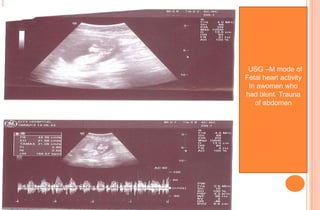

USG PICTURES OF ABDOMEN OF

A PREGNANT WOMEN WITH

BLUNT TRAUMA OF ABDOMEN

USG –M mode of

Fetal heart activity

In awomen who

had blunt Trauna

of abdomen

USG PICTURES OFABDOMEN OF A PREGNANT WOMEN WITH BLUNT TRAUMA OF ABDOMEN

USG –M modeof Fetal heart activity In awomen who had blunt Trauna of abdomen